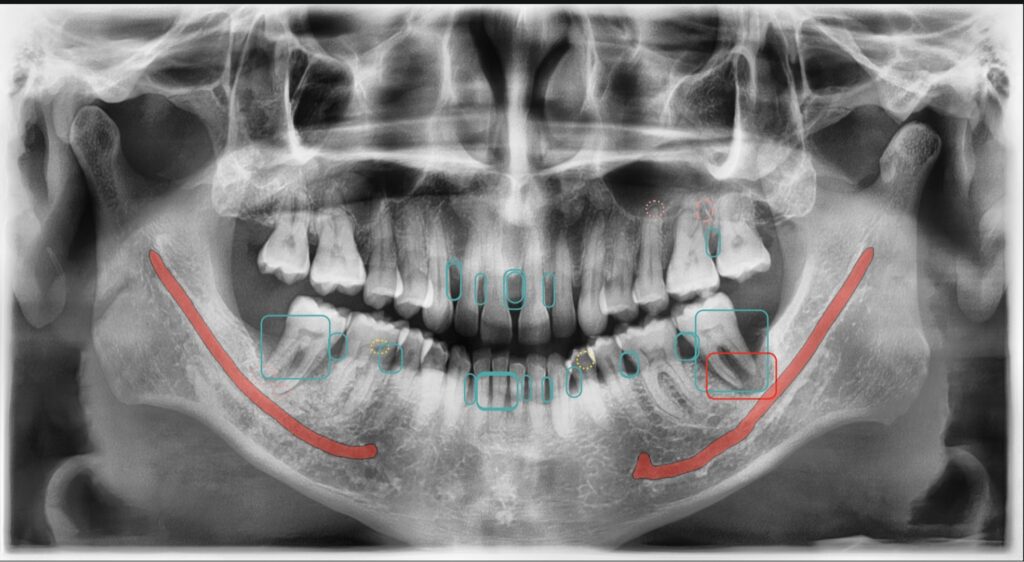

RX PANORÁMICA + ESCANEO DENTAL + DIAGNOSTICOS $118.000